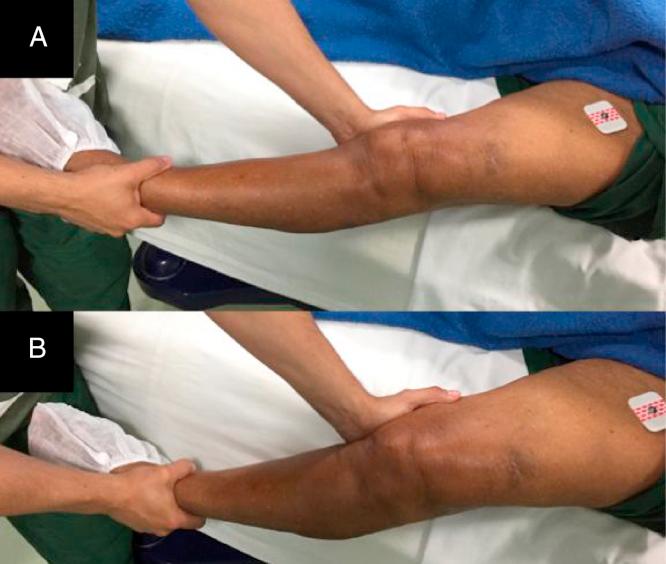

For decades, the main cause of failure in total knee arthroplasty (TKA) is still the malalignment of prosthetic components. The authors present a case of advanced knee arthrosis, treated by TKA. Preoperative planning was performed with a mobile application and the patient was submitted to primary TKA using an implant developed with inspiration from the theory of "modified GAP" with a rotated tibial tray. Neutral mechanical alignment of the lower limbs was obtained and the application proved to be viable regarding its proposed plan for this case.

几十年来,全膝关节置换术(TKA)失败的主要原因仍然是假体组件排列不齐。作者介绍了一例晚期膝关节骨性关节炎患者,采用TKA进行治疗。术前使用移动应用程序进行规划,并使用一款受“改良GAP”理论启发开发的带有旋转胫骨托的植入物对患者实施初次TKA。实现了下肢的中立机械对线,并且该应用程序在针对此病例的拟议计划方面被证明是可行的。